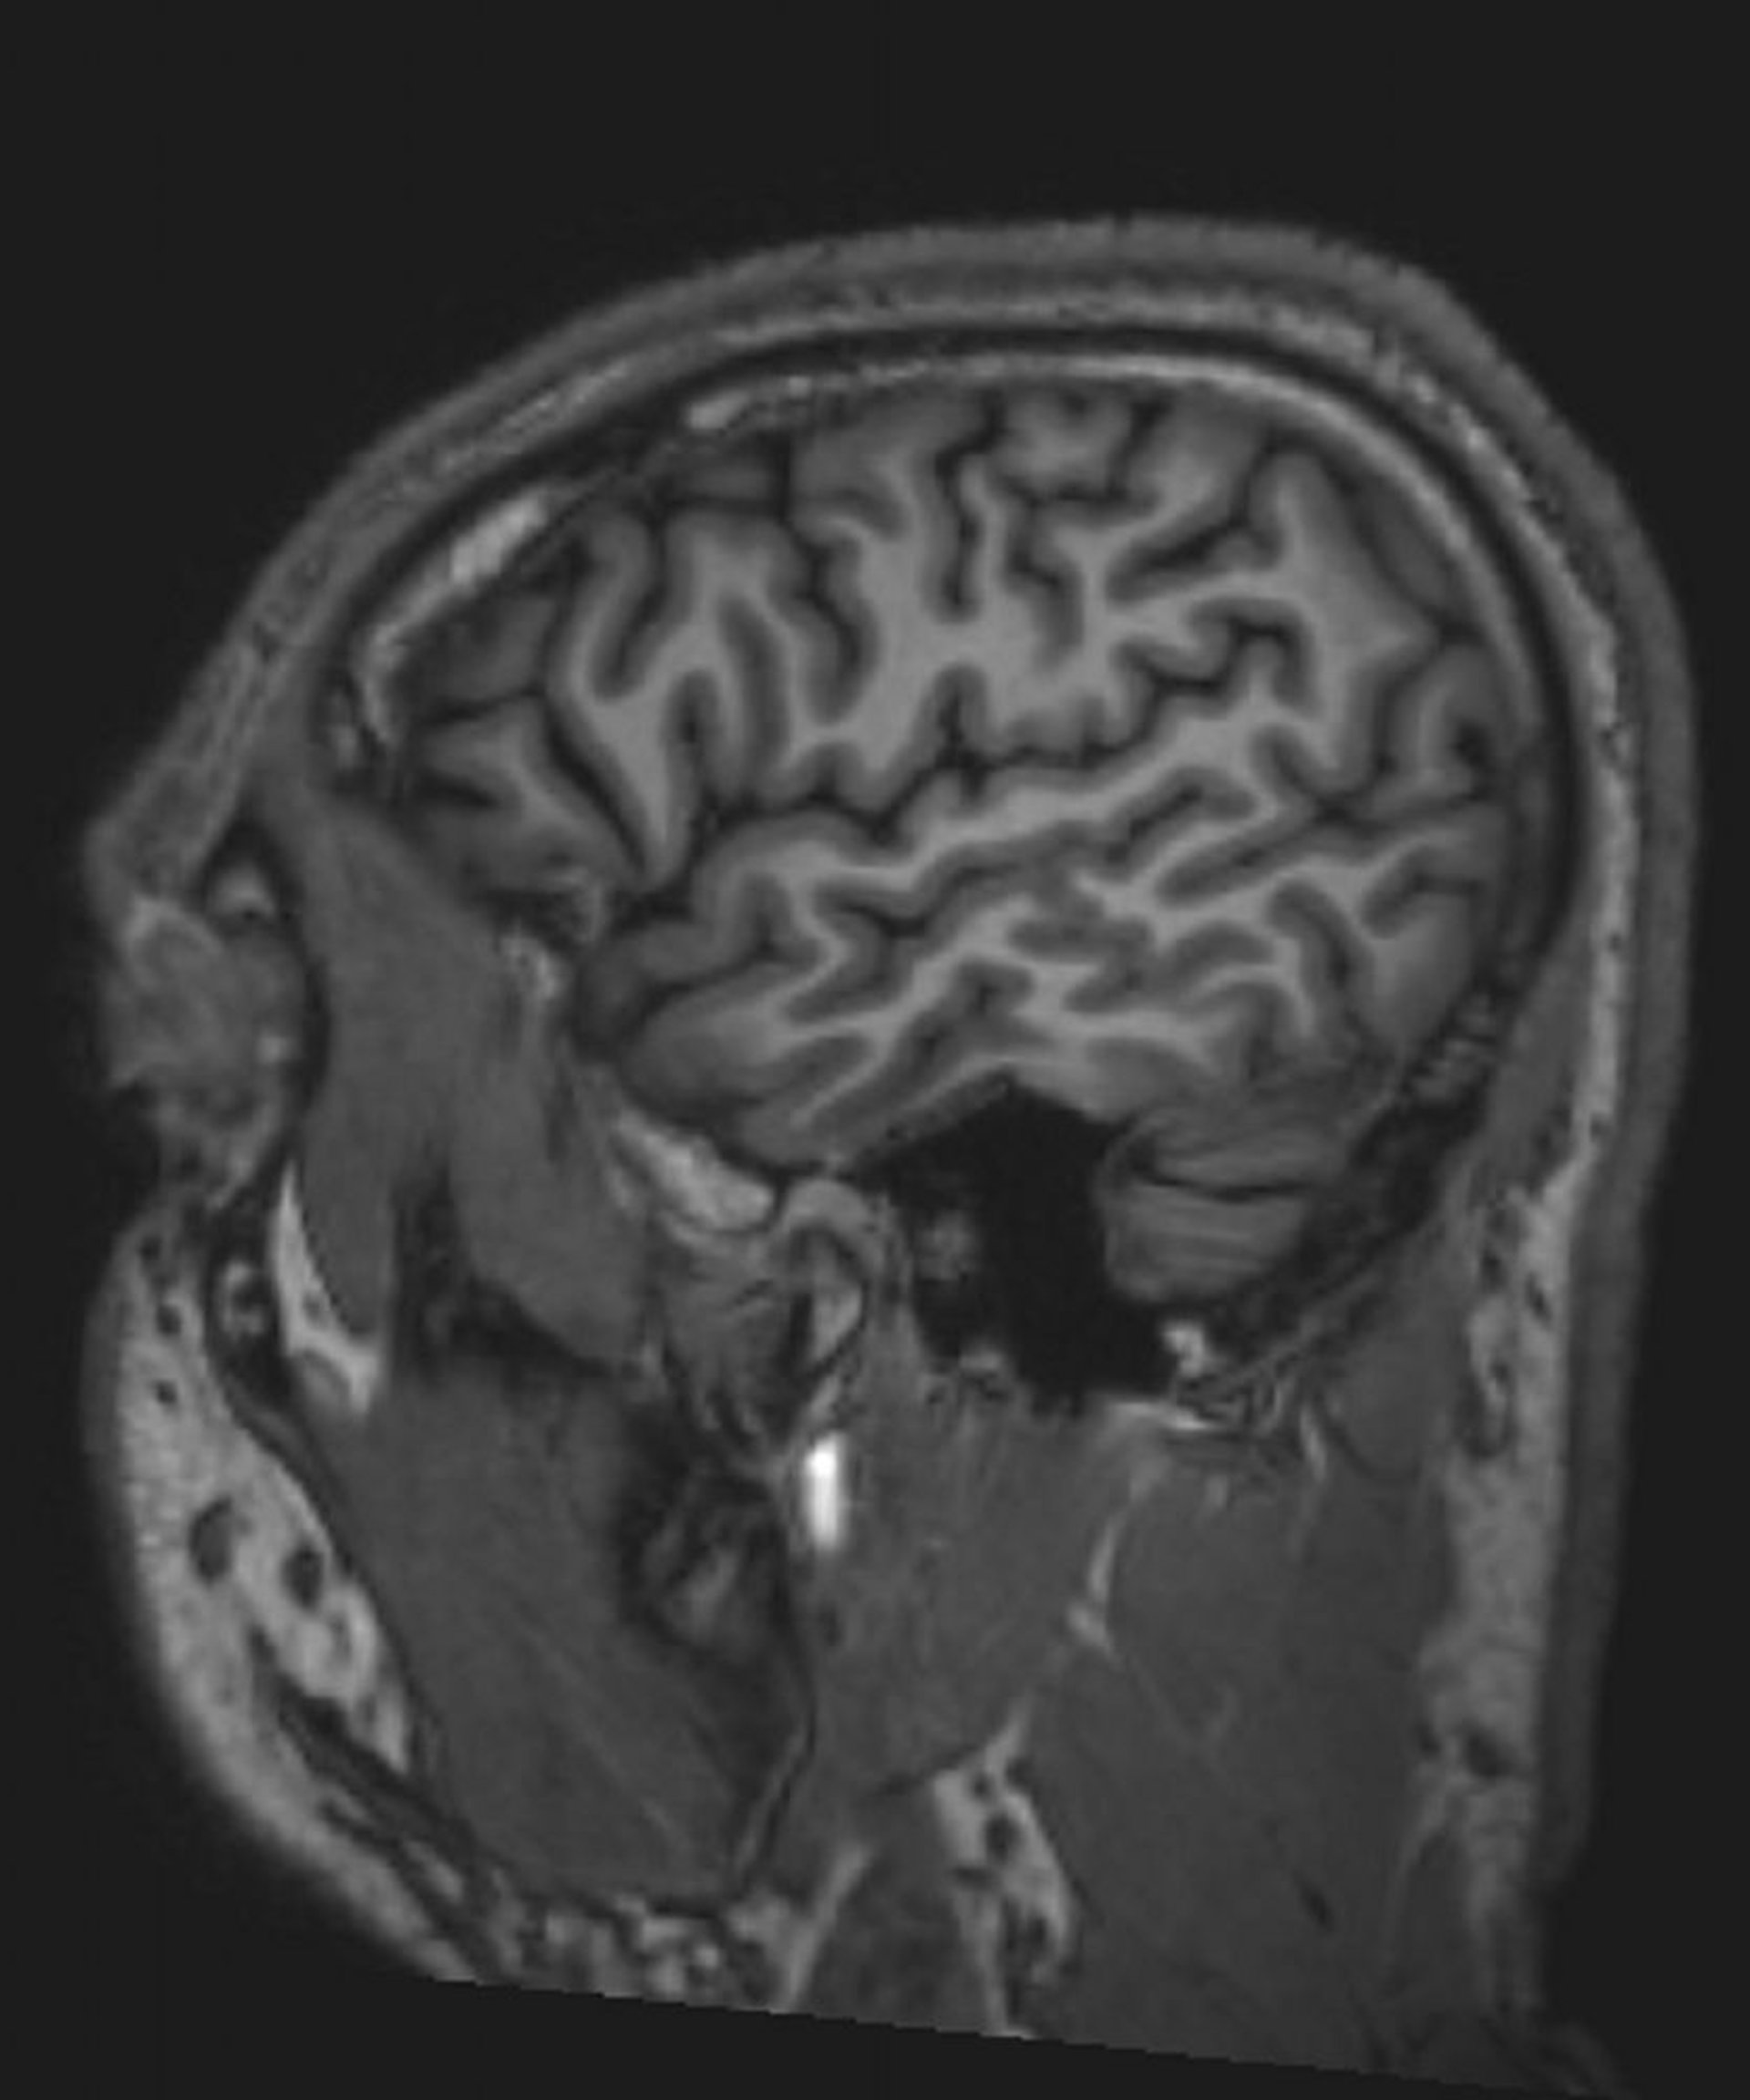

正常な脳MRI画像(矢状断像)―スライド1

© 2017 Elliot K.Fishman, MD.

神経疾患におけるMRI